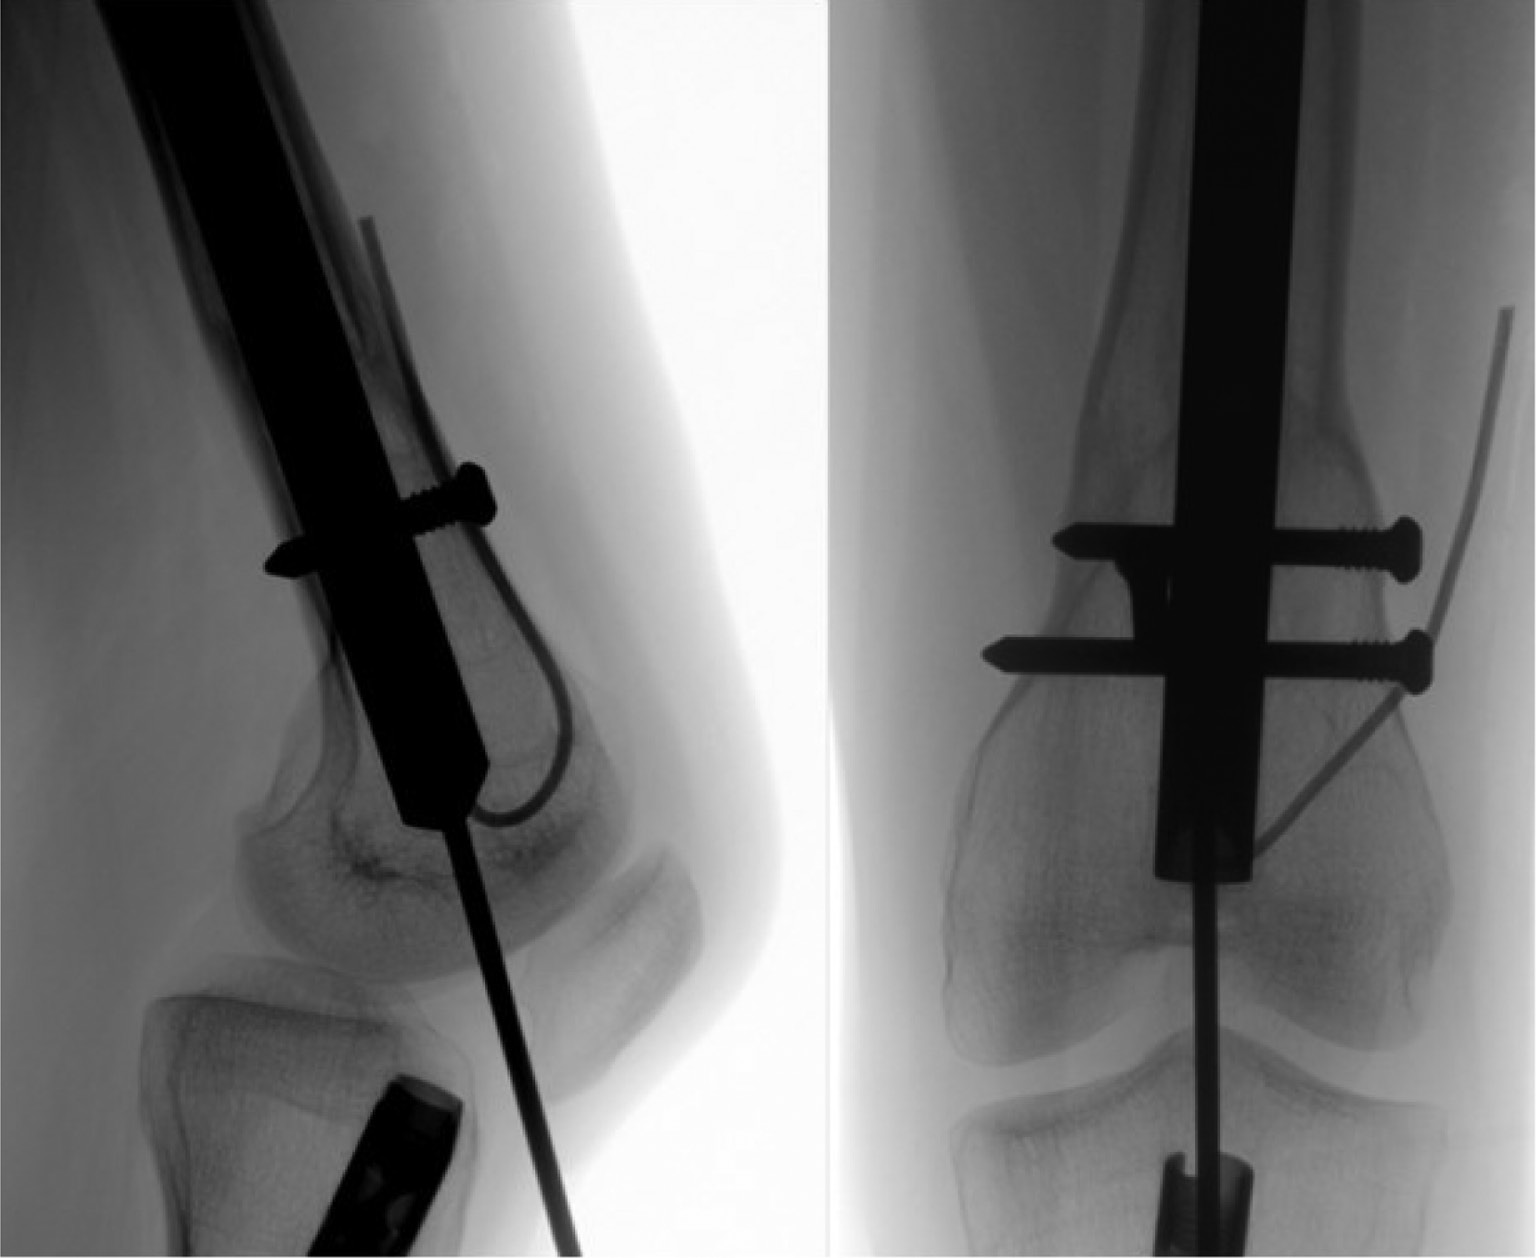

Removal of Retrograde Femur (Fitbone® Motorized Nail)

1. After positioning the patient properly (see above Figure 16), the first step of the surgery is to remove the receiver (Figure 17). Typically, the original incision can be used even if the receiver was placed proximally. The receiver cable and the connector are located subcutaneously and dissected proximally under the skin (Figure 18). The cable is cut approximately 3 cm distal to the connector where the cable becomes thin again (Figure 19). Key Tip: Leaving the cable long enough is helpful to allow it to be pulled out through the knee joint later in the procedure (Figure 20). Once identified, the receiver can be pulled out with a Kocher clamp (Figure 21). If the receiver cannot be reached from the original incision site, a separate incision over the receiver can be made. Once identified through the new incision, the cable is cut and the rest of the cable is removed through the original incision as described above.

2. The next step is the removal of the pegs/screws. Usually, an incision at the original insertion site can be used. The exact position of the pegs/screws is localized by fluoroscope (Figure 22). Like the magnetic nail, the proximal screw/peg is removed percutaneously by dissecting through the fascia and muscle down to the screw head. The cannulated screwdriver with the threaded cannula can then be used to capture the threads inside the screw head. It is important not to force the threaded cannula into the screw head. Holding the screwdriver at the correct angle to prevent breakage of the threaded cannula in the peg/screw head is also important. The peg/screw is turned counterclockwise while simultaneously pulling the peg/screw out.

Figure 16. Position the patient with a towel bump or sterile triangle to allow knee flexion to about 60 degrees.

jposna20220031_fig16.jpg

Figure 22. The exact position of the pegs/screws is localized by fluoroscope. The proximal screw/peg is removed percutaneously by dissecting through the fascia and muscle down to the screw head.

jposna20220031_fig22.jpg